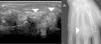

An 80 year-old male patient with a history of controlled high blood pressure, presented with a lesion in the dorsal region at the base of his third finger of the right hand, of several months duration. Physical examination of the lesion revealed that it was of solid consistency and partially deep layer attached. It was therefore diagnosed as a soft tissue tumor. An ultrasound scan was requested which detected a soft tissue mass with diffuse echotexture (Fig. 1A). In view of these findings, CT and MR scans were performed. From these tests we observed that the tumor had a lobulated morphology, contained calcifications and eroded the adjacent bony surfaces (Figs. 1B and 2). The tumor enhanced heterogeneously following the administration of intravenous line contrast dye. As a result of these findings, we decided to perform a biopsy in which uric acid crystals were detected, confirming the diagnosis of arthropathy by crystal deposits (Fig. 3).